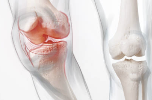

② 퇴행성 관절염 증상 완화

초기 무릎 골관절염 환자에게서 통증 감소와 기능 향상 효과가 나타났다는 연구들이 다수 보고돼 있습니다.

특히 관절의 뻣뻣함, 통증, 부기 완화에 도움을 줍니다.

④ 관절 염증 억제

글루코사민은 사이토카인 및 프로스타글란딘 같은 염증 유발 물질의 생성을 억제해 관절 내 염증 반응을 줄여줍니다.

⑥ 연골 마모 방지

관절에서 연골이 닳아 없으면 뼈와 뼈가 직접 마찰되어 통증이 발생합니다.

글루코사민은 이 연골층의 손상을 늦추고 보완하는 역할을 합니다.